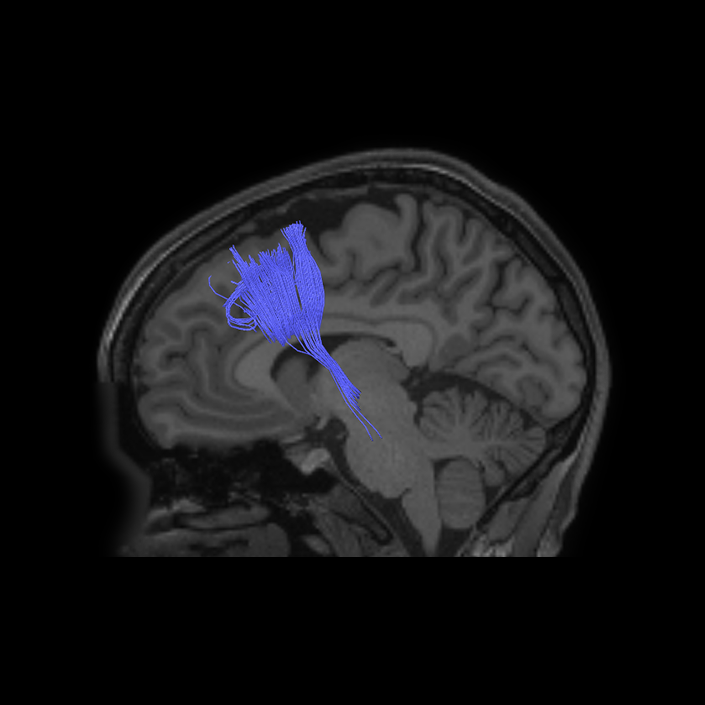

ᐅ SummaryArea SFL: part of the supplementary motor regions. Known to be hemispherically asymmetric. Specifically, the left hemisphere shows more activity when listening to stories and when a participant is matching objects based on a verbal cue. Compared to area 8BL, area SFL shows more activation when listening to a story, matching objects based on verbal cues and in social interaction settings. Compared to area s6-8, area SFL shows more activation in the left hemisphere when individuals listen to a story. In the right hemisphere, area SFL is activated insocial interaction settings and is deactivated during object feature comparison tasks. ᐅ Where is it?Area SFL (superior frontal language area) is located on the posterior medial SFG straddling over the interhemispheric cleft. ᐅ What are its borders?Area SFL borders SCEF inferiorly. Its anterior inferior neighbor is area 8BM and its anterior superior neighbor is area 8BL. Areas 6ma and s6-8 are its lateral neighbors. ᐅ What are its functional connections?Area SFL demonstrates functional connectivity to areas 8BL, 8AV, 9a, 9p, and 9m in dorsolateral frontal lobe, areas 8BM, d32, areas 44, 45, 47L, and 47s in the inferior frontal lobe, area 55b in the premotor areas, areas STSda, STSdp, STSva, STSvp, TE1a, and TGd in the temporal lobe, area PGi in the lateral parietal lobe, and areas 31pv, and 31pv in the medial parietal lobe. ᐅ What are its white matter connections?Area SFL is structurally connected to pyramidal tracts, the frontal aslant tract and contralateral hemisphere. Connections to pyramidal tracts descend through the posterior limb of the internal capsule and cerebral peduncle to the brainstem. The FAT connects SFL with the inferior frontal gyrus, terminating at parcellations 44, IFSp and MI. Contralateral connections course through the body of the corpus callosum to SCEF and 8BL. Local short association fibers connect with SCEF, 8BL, SFL and 6ma. ᐅ What is known about its function?Area SFL was subdivided from adjacent parcellations due to differences in myelin thickness and functional activity. Area SFL is known to be hemispherically asymmetric. Specifically, the left hemisphere shows more activity when listening to stories and when a participant is matching objects based on a verbal cue. Compared to area 8BL, area SFL shows more activation when listening to a story, matching objects based on verbal cues and in social interaction settings. Compared to area s6-8, area SFL shows more activation in the left hemisphere when individuals listen to a story. In the right hemisphere, area SFL is activated in social interaction settings and is deactivated during object feature comparison tasks. |

A: lateral-medial

B: anterior-posterior

C: superior-inferior

DTI image |